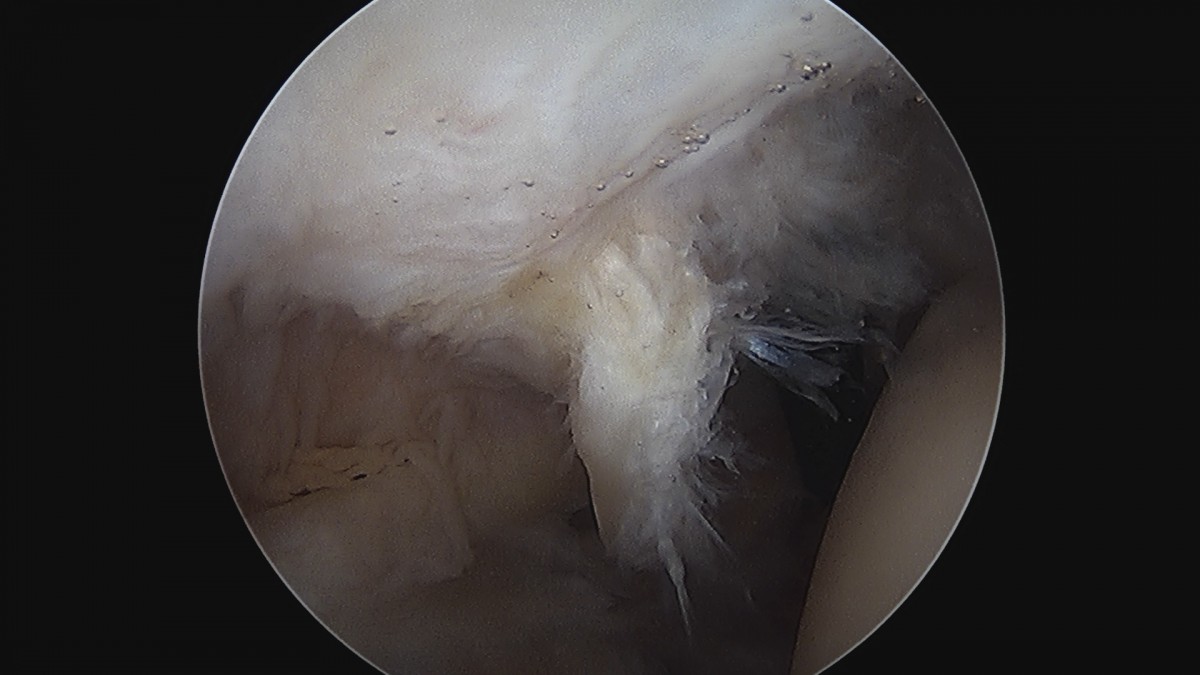

정지영원장님 어깨 회전근개 봉합술 임채O 환자

dae765e4d9ac96aee867c9d6292d8784_1758009114_2696.jpg